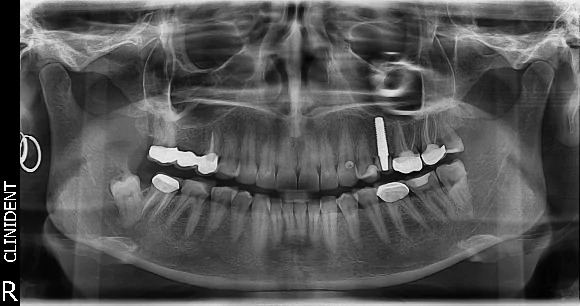

A szájsebész pedig a kihúzott fog helyére egy egyrészes cirkon implantátum behelyezését javasolta, melyre kielégítő primer stabilitás esetén természetes és elegáns megjelenésű ideiglenes korona készítését helyeztük kilátásba.

Az implantátum beültetés során elért megfelelő primer stabilitásnak köszönhetően a beavatkozással egyidőben ideiglenes korona is készülhetett az implantátumra.

Ebben az esetben az azonnali, szék melletti, vagyis rendelőben készülő változatát készítettük el.

A hídcsere és tömések a gyógyulási időszakban, míg a végleges cirkon fog az implantátum csontosodása után készülhetett el.

A páciens által elfogadott kezelési tervvel nem csak a megfelelő szájhigiéniát, de a rágófunkciót és az esztétikumot is sikeresen helyreállítottuk. A teljes kezelés 8 hónapot vett igénybe.